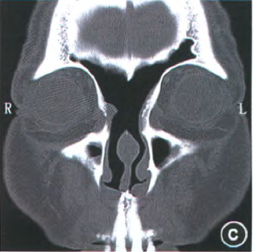

圖片顯示DraffIII型手術(shù)后寬大的額竇引流通道及清楚的暴露了前顱底